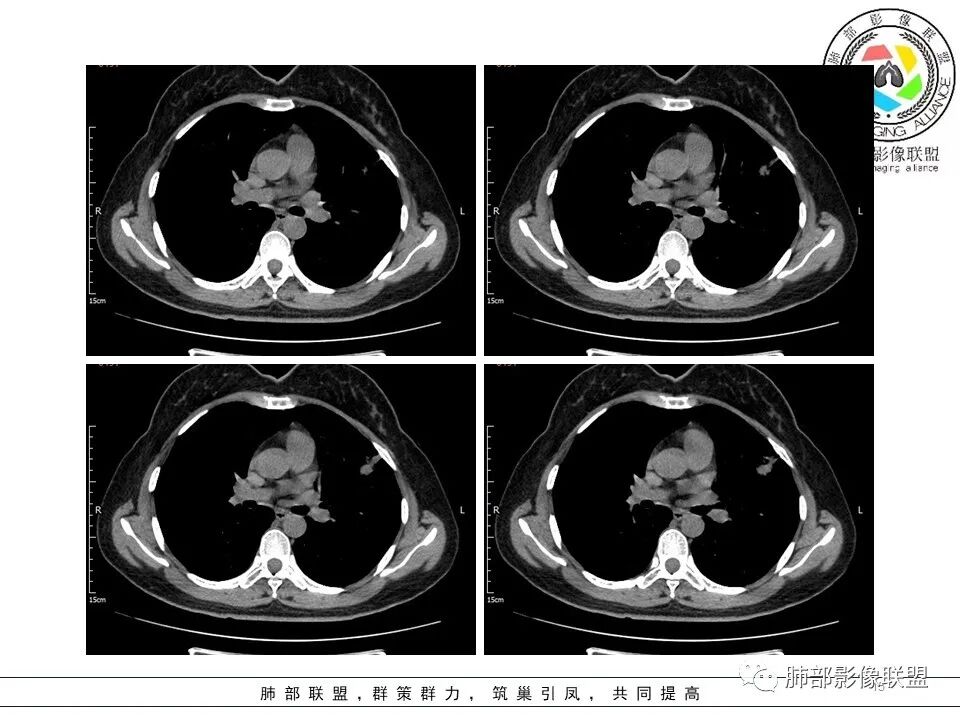

一.大结节影像特点:

左肺上叶胸膜下不规则结节影,分叶、粗短毛刺,胸膜牵拉等,像个“刺头”。

未见钙化,也未显示液化坏死或空洞。

与支气管相关,但取层未能显示支气管进入情况。

有几点应当引起我们高度重视:

1.病灶周围向几个方向膨出的边界清楚的磨玻璃影,这些磨玻璃影时隔几个月依然,几乎可以排除出血及一般的炎性改变。

2.病灶的胸膜牵拉线与其间病灶胸膜侧的磨玻璃边构成朝向胸壁的“月牙铲”结构,这种影像学表现某种程度上反映出病理学特征——病灶收缩+小叶间隔阻挡。

3.病灶实性密度区强化明显,这有助于我们区分一些其他类似病灶,如结核灶等!

4.邻近未见树芽征及卫星灶等。

结合临床,应当高度怀疑浸润性肺腺癌!